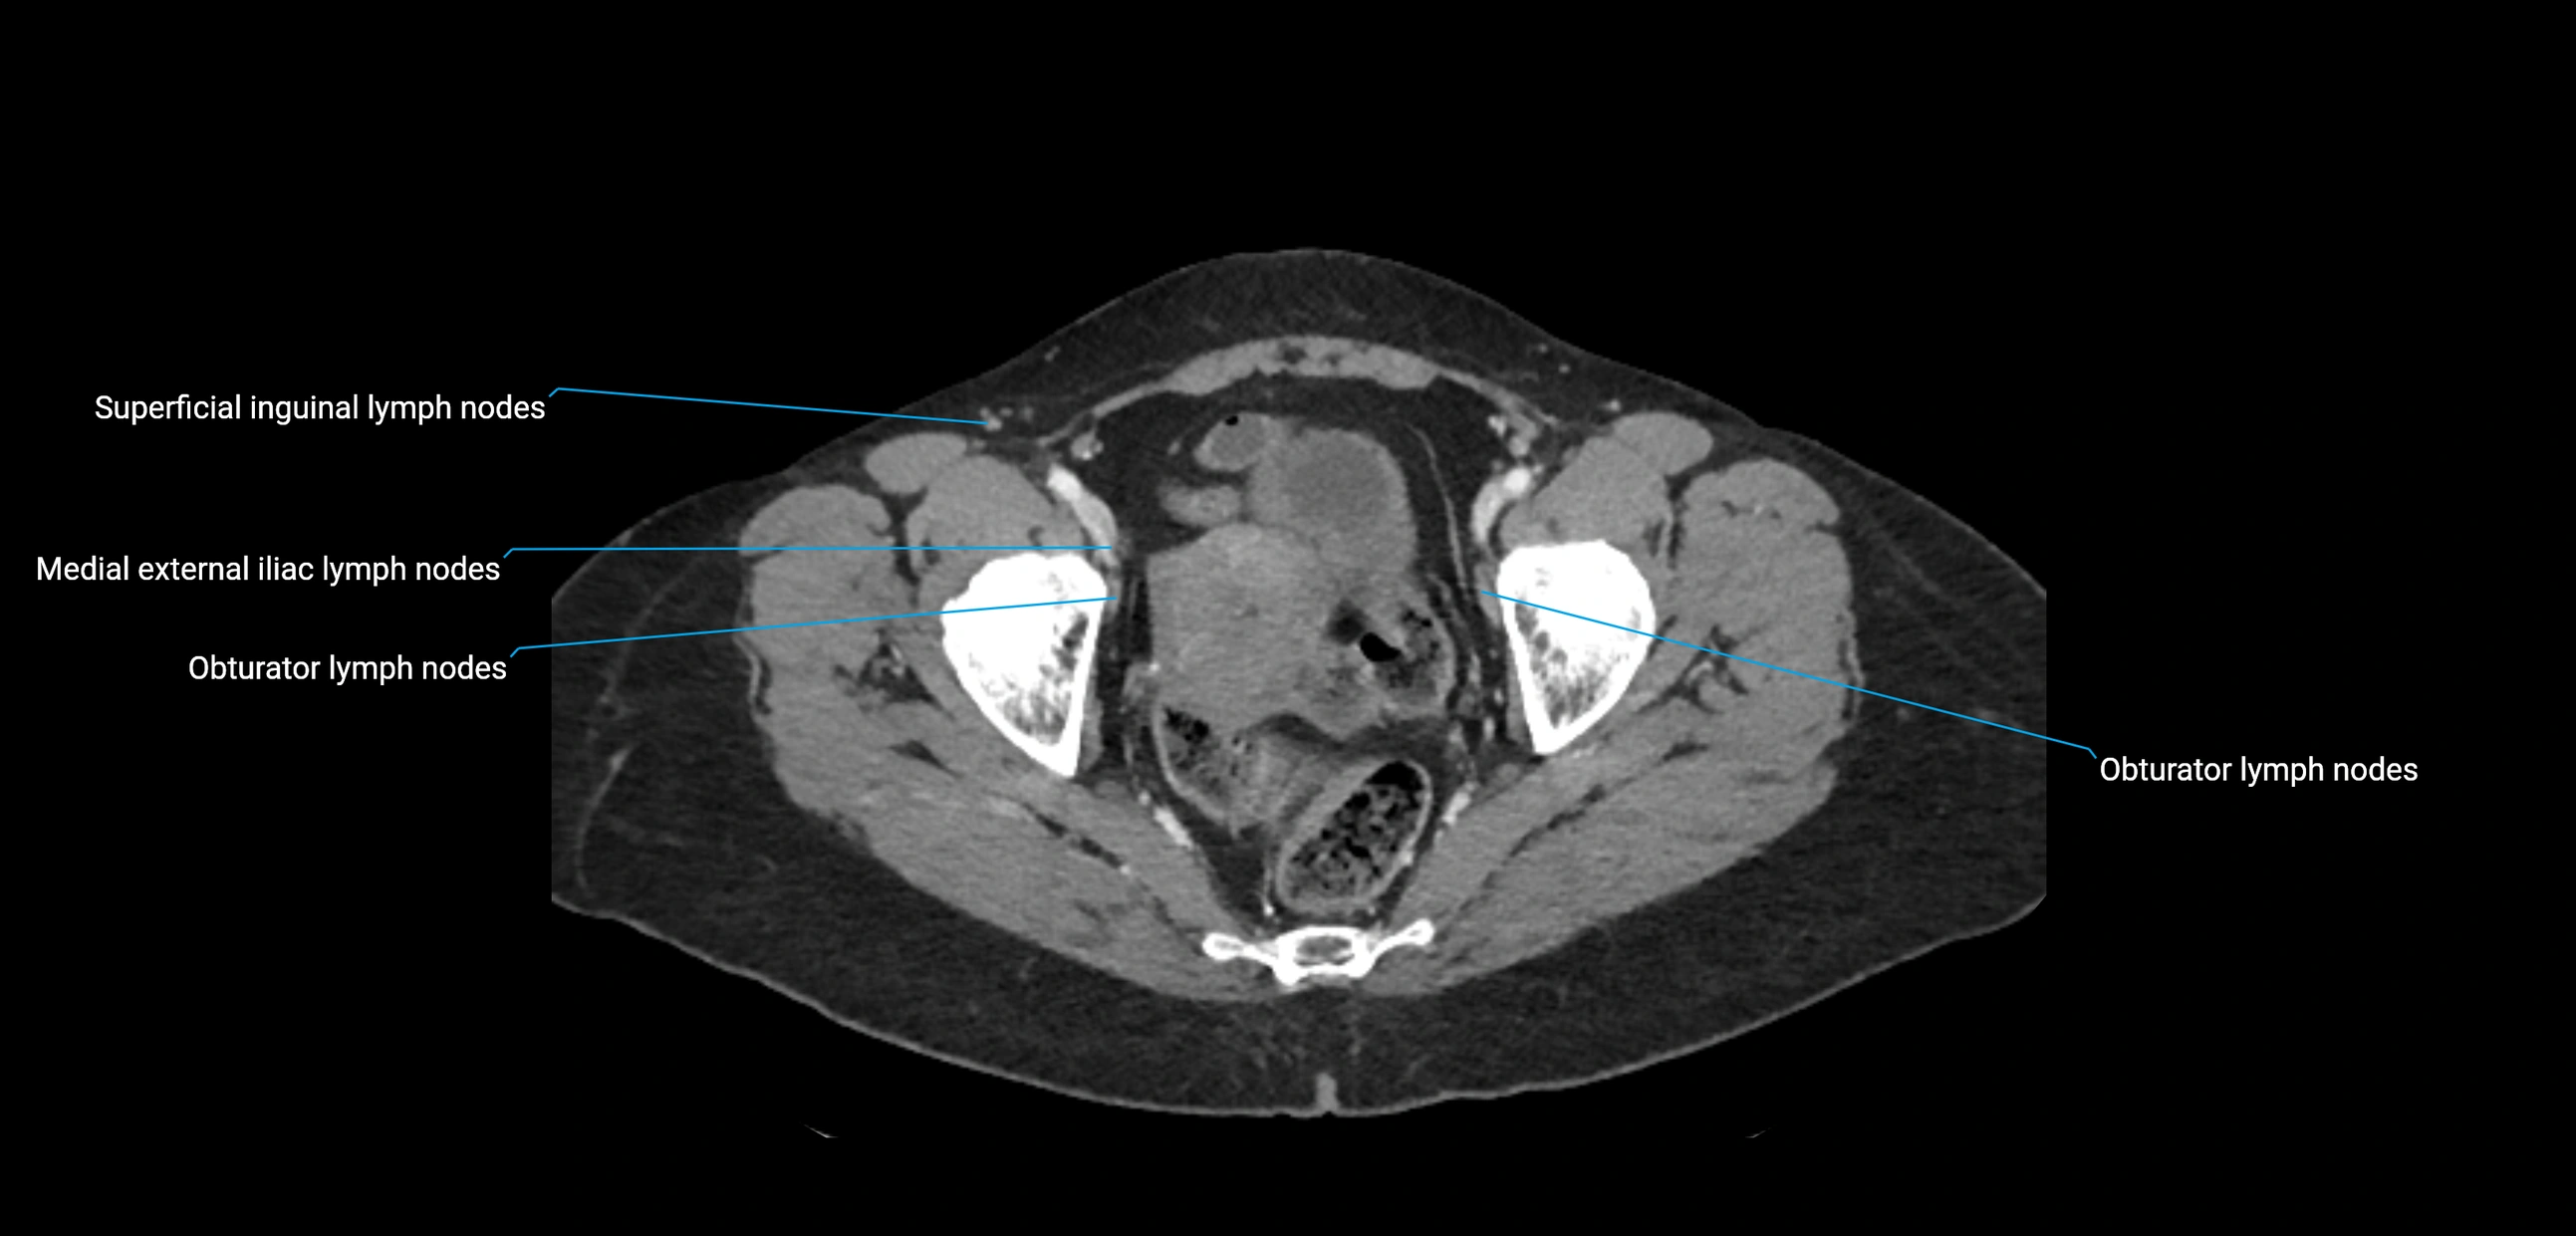

These nodes receive lymph from a wide range of abdominal and pelvic structures. Specifically, they drain lymph from the kidneys, suprarenal glands, gonads (testes/ovaries), uterus, uterine tubes, and pelvic organs, before converging into the lumbar lymphatic trunks, which terminate in the cisterna chyli → thoracic duct.

Clinically, the lateral aortic lymph nodes are critically important in oncology, being involved in the spread of testicular cancer, ovarian cancer, endometrial cancer, cervical cancer, renal malignancies, and retroperitoneal lymphomas. They are also key targets in retroperitoneal lymph node dissection (RPLND) for testicular tumors.

CT Appearance

CT Post-Contrast:

• Normal nodes enhance homogeneously

• Malignant nodes may show heterogeneous enhancement, central necrosis, or conglomerate formation

• Size >1 cm short axis is suspicious, though morphology and distribution are equally important

CT Venography (CTV):

• Demonstrates nodal encasement or compression of adjacent vessels (aorta, IVC, renal veins)

• Useful in staging testicular and ovarian malignancies

• Provides 3D reconstructions for retroperitoneal lymph node dissection planning